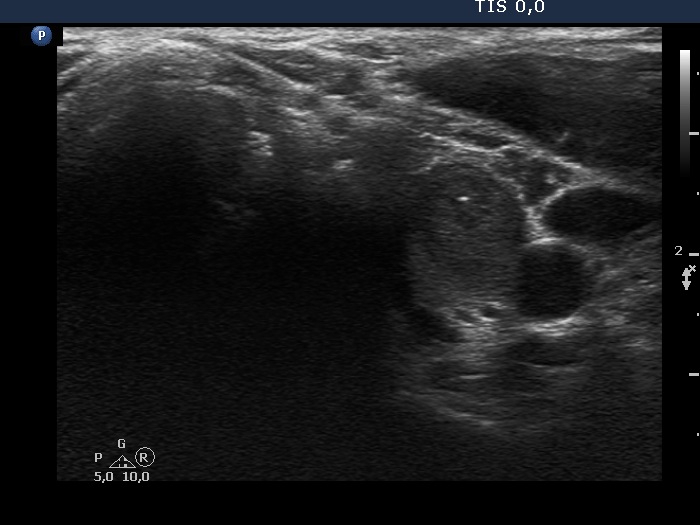

Ultrasonography. The thyroid was echonormal. There were two nodules in the left lobe. The upper, minimally-moderately hypoechoic showed taller-than-wide sign and had two microcalcifications. The lower nodule was a dominantly echonormal lesion. This showed an incomplete halo and signs of perinodular blood flow. The volume of the nodules has not been changed since their recognition.